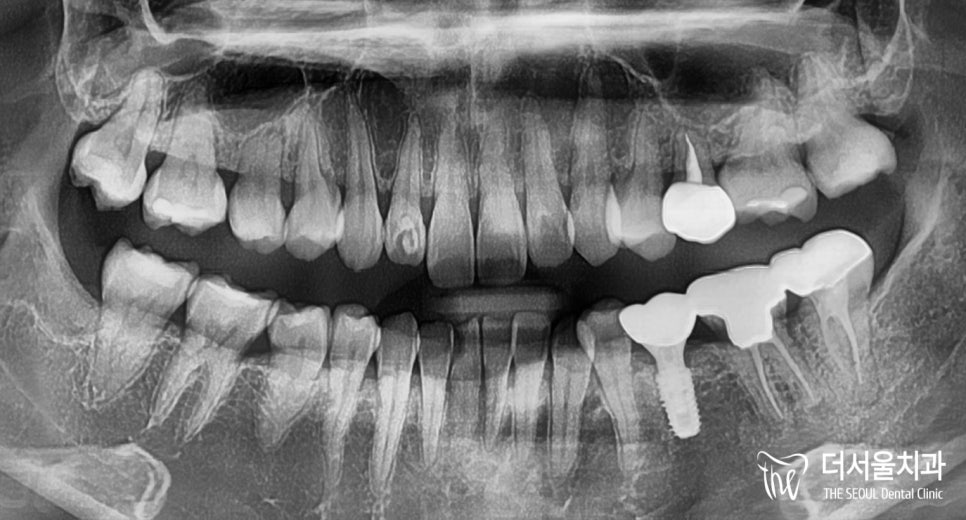

튼튼히 픽스처를 심어드린 뒤에

뼈와 골유착을 이뤄 고정될 수 있도록

시간을 가졌습니다.

골유착이 잘 이뤄졌다면,

그 위로 제작된 크라운을 시적합니다.

이번 케이스도 마찬가지로

지르코니아 재료로 제작된 것을

세팅해드렸습니다.

# 35 자리 소구치

20대 임플란트 수술은 잘 끝났습니다.